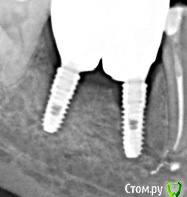

Eddie Опубликовано 29 октября, 2017 Поделиться Опубликовано 29 октября, 2017 (изменено) Здравствуйте. Ситуация такая- установлен имплантат Осстем, торк при установке 35-40+ Фдм+ сст вестибулярно. Заглубил на 1-1.5 мм. Сделал снимок сразу после! Через 4 месяца пациент приходит с такой картиной! Жалоб не было, десна бледно-розовая. Дал торк на закручивание 30н, все в порядке. Чего ожидать далее, каков прогноз? Можно ли протезировать?И главное, как этого избежать в дальнейшем, в чем причина, придавил кость фдм-кой, перегрел? Помню, что не использовал кортикальную фрезу. Изменено 29 октября, 2017 пользователем Eddie Ссылка на комментарий

TIGER Опубликовано 1 ноября, 2017 Поделиться Опубликовано 1 ноября, 2017 Здравствуйте. Ситуация такая- установлен имплантат Осстем, торк при установке 35-40+ Фдм+ сст вестибулярно. Заглубил на 1-1.5 мм. Сделал снимок сразу после! Через 4 месяца пациент приходит с такой картиной! Жалоб не было, десна бледно-розовая. Дал торк на закручивание 30н, все в порядке. Чего ожидать далее, каков прогноз? Можно ли протезировать?И главное, как этого избежать в дальнейшем, в чем причина, придавил кость фдм-кой, перегрел? Помню, что не использовал кортикальную фрезу.кортикальной фрезой отработали или после финишной имплант? Ссылка на комментарий

Eddie Опубликовано 1 ноября, 2017 Автор Поделиться Опубликовано 1 ноября, 2017 (изменено) кортикальной фрезой отработали или после финишной имплант?Без кортикальной, хотел получить торк для ФДМ Изменено 1 ноября, 2017 пользователем Eddie Ссылка на комментарий